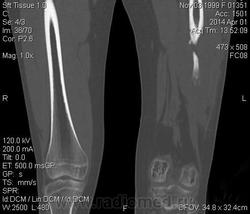

Молодая дама (14 лет) с переломом срдней трети диафиза левого бедра в анамнезе (декабрь 2012 г). Ломала ногу несколько раз в этом месте. Сейчас состояние после МОС. Как следует понимать изменения в кости, формируется ли ложный сустав?

Похоже ложный сустав сформировался. Но при нём обычно большие напластования костной мозоли, здесь их нет. В таких случаях смотрю при скопии подвижность.

Ох, не хочется думать о ложном суставе в 14 лет... По срокам под ложный сустав подходит, он характеризуется замыканием костномозгового канала с формированием подобий суставных поверхностей. У нее же есть хиленькая периостальная костная мозоль по задней поверхности бедра удерживающая отломки в правильном положении. Я склонна думать, что это скорее застарелый перелом (оно же замедленная консолидация). Здесь очень важно посмотреть предыдущие снимки (поиск рефрактуры, либо отсутствия полной консолидации).

Настоящего, родного ложного сустава пока нет, хотя костномозговой канал дистального отломка уже закрыт - образовалась склерозированная замыкательная пластина. Варусная деформация почти в 165 градусов... Я бы заключилась неполной консолидацией и варусной деформацией, прогностически формирование ложного сустава очень вероятно.